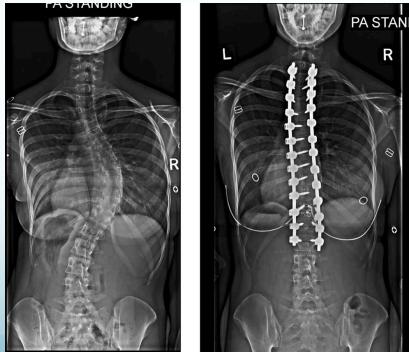

Surgical Treatment

Indications:

- Curves >40° in skeletally immature patients

- Progressive curves

Procedure:

- Correction

- Instrumentation

- Fusion

- AP and LAT of entire spine (Cobb angle measurement)

- AP pelvis (Risser grade)

Cobb Angle Measurement

- Select most tilted vertebrae above and below curve apex

- Angle between intersecting lines drawn perpendicular to superior vertebra top and inferior vertebra bottom

Surgery

- Adult documented progressive curves